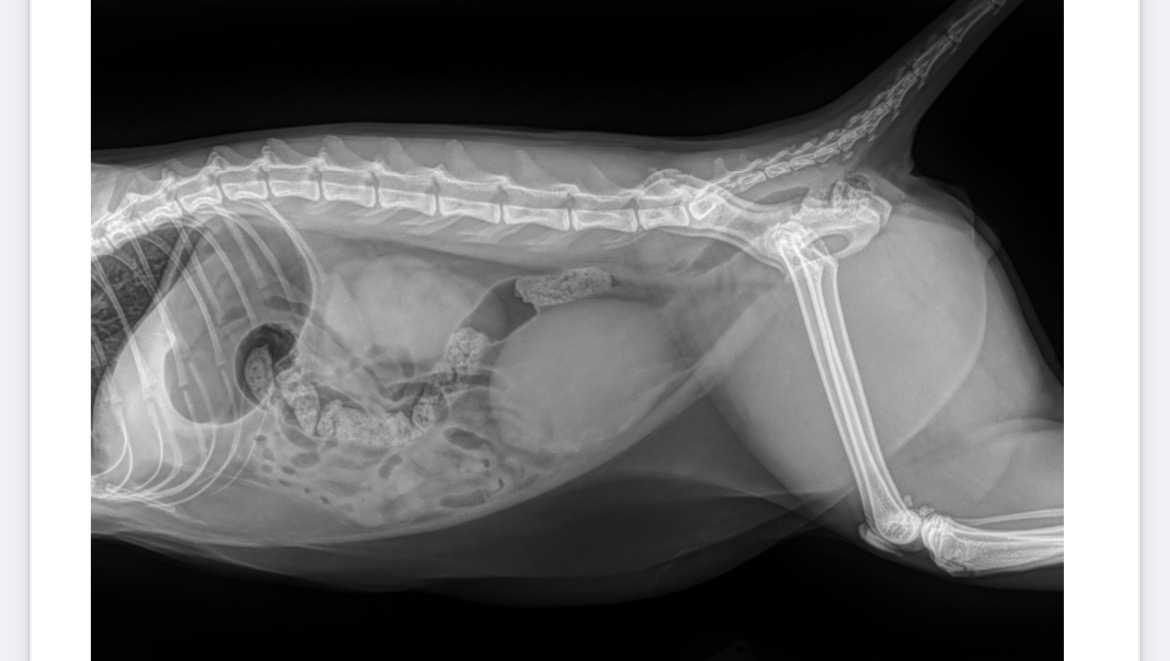

Hi all, Rose here…most of y’know my cat #2 Boba as my baby boy. He means the world to me but he was rushed to the vet due to bleeding and not eating! I have never asked for handouts before, I really don’t like to… sigh but I was dumb not to get pet insurance and he fell into a costly emergency — which seemed to be UTI at first but now has escalated to stones blocking his pee pee hole. He needs to be monitored overnight while he has a catheter in and this is only months after my dad fought kidney stones which is pretty similar as a human condition. The estimated Vet + ER bill is over 5K but I’m seeking some help from friends and family ext. that can give anything to lessen my burden as I’m already in so much debt. Thanks in advance & I appreciate you reading this! Boba will thank you too.

*Quick update: he is under observation at Mash and most likely need 2-3 nights stay. It is borderline life threatening and it’s really hard to hear this news. He’s only 1.5 yrs old, my little baby boy is already hospitalized.